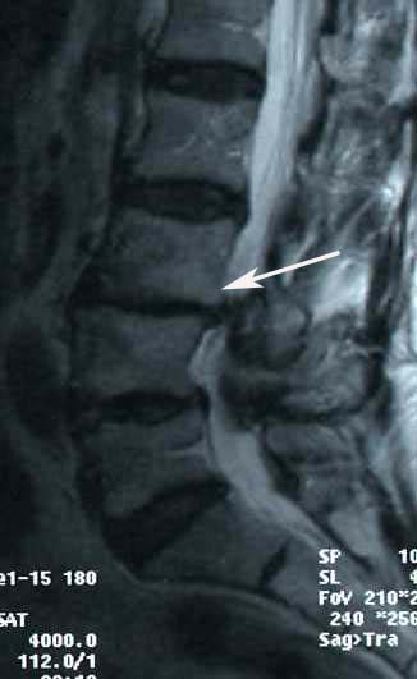

| МРТ поясничного отдела позвоночника. Ретролистез L3 позвонка. Стрелкой указано смещение L3 позвонка кзади. | |

Диагноз спондилолистеза устанавливается на основании расспроса пациента о его жалобах и развитии заболевания (анамнеза), оценки неврологических симптомов (определении зон пониженной чувствительности, снижения выраженности сухожильных рефлексов, снижения силы в отдельных мышцах), данных ренгенографии и МР томографии. Золотым стандартом среди методов визуализации межпозвонковой грыжи диска является Магнито-Резонансная Томография (МРТ). Именно этот метод наиболее адекватно отражает состояние спинного мозга и позвоночника, а также способен точно диагносцировать степень и причину листеза. Необходимо отметить, что качество изображения вашего позвоночника на томограмме зависит от такого показателя аппарата, как напряженность магнитного поля. В настоящий момент для получения хороших МР снимков этот показатель должен равняться 1,5 Тесла. Аппараты с меньшей напряженностью магнитного поля, а также данные Компьютерной Томографии (КТ) дают нечеткую картинку и затрудняют выбор метода лечения для нейрохирурга.